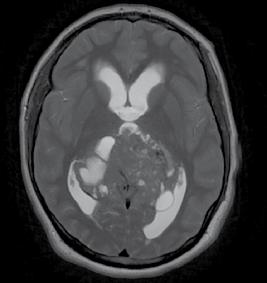

This issue includes six diverse, peerreviewed articles spanning rare case reports and forward-looking reviews. They include a rare presentation of immune checkpoint inhibitor-associated hydropneumothorax; a recurrent, aggressive, solitary plexiform neurofibroma with KRAS and AKT1 alterations; and a compelling case of unresectable giant pinealoblastoma responding favourably to induction chemotherapy followed by craniospinal radiotherapy. We also highlight a review of CAR-T cell-based immunotherapeutic strategies in hepatocellular carcinoma, a clinically significant case of aggressive angiomyxoma in term pregnancy, and a multi-omics exploration in non-small cell lung cancer aimed at advancing biomarker and pathway discovery.

In this context, over the past years, clinical activity of MEK inhibitors in NF1associated PNFs has been demonstrated, with meaningful reductions in tumour volume and symptom burden (particularly in children), whereas earlier attempts with imatinib, cabozantinib, miR farnesyltransferase inhibitors, or mTOR inhibition achieved only modest disease stabilisation.15 Extrapolating from this biology, trametinib was used to counteract KRAS-driven MAPK activation as selumetinib was unavailable in the authors’ country. Pazopanib, which targets vascular endothelial growth factor receptor/platelet-derived growth factor receptor/fibroblast growth factor receptor,

Figure 2: Rat sarcoma–MAPK and PI3K–protein kinase B–mTOR signalling with candidate therapeutic targets.

Dysregulation of RAS–MAPK and PI3K–AKT–mTOR signalling can drive proliferation; candidate drug targets are shown. AKT: protein kinase B; cAMP: cyclic adenosine monophosphate; ERK: extracellular signal-regulated kinase; GDP: guanosine diphosphate; GTP: guanosine triphosphate; MEK: mitogen-activated protein kinase kinase; RAS: rat sarcoma; RAF: rapidly accelerated fibrosarcoma serine/threonine-protein kinase; SOS: son of sevenless protein; TKR: tyrosine kinase receptor.

was combined, given the pronounced vascularity and the expectation that reducing angiogenic signalling and stromal support could enhance disease control, which has been demonstrated in soft-tissue sarcomas.16 The combination achieved a partial radiological response consistent with pathway plausibility; however, durability was limited by toxicity and access constraints, underscoring real-world barriers even when a coherent biological strategy is available.

Given these considerations and the lesion’s unresectability, an alternative treatment with cisplatin-based chemoradiotherapy was considered despite not being recommended for NF1-related PNFs due to the risk of radiation-induced malignancy in susceptible tissues.15 However, as this was an unresectable isolated PNF with substantial symptoms, it was considered the best option after a multidisciplinary review and explicit consent from the patient, attending to organat-risk constraints and malignancy risk.17

Given the limited benefit this regimen provided, and without any options left in the authors’ country, referral to the NIH UDN was considered; however, the COVID-19 pandemic delayed the patient’s travel until 3 years after her initial presentation. After a comprehensive review, it was determined that it was indeed a solitary PNF, for which surgery remained the most promising option for durable local control. However, active surveillance was favoured given the current performance status and competing risks.18

This report has several limitations. Pathology material from childhood procedures performed abroad was unavailable, precluding central histopathological review and comparison across time. Access to MEK inhibitors formally approved for NF1PNF (e.g., selumetinib, mirdametinib)19 was constrained in this setting, which influenced

References

1. Friedman JM, "Neurofibromatosis 1," Adam MP et al (eds.), GeneReviews® [Internet] (1993) Seattle: University of Washington. Available at: http://www. ncbi.nlm.nih.gov/books/NBK1109/. Last accessed: 22 September 2025.

therapeutic choices. Although trametinib combined with pazopanib achieved a partial response, the experience reflects off-label use and should be interpreted cautiously; in similar cases, MEK inhibitors or multikinase inhibitors (e.g., cabozantinib) may be considered according to the tumour’s mutational profile, access, and risk–benefit assessment. However, from a patient-centred perspective, and acknowledging the scarcity of consensus documents specific to isolated PNF, it was considered that supportive care was not ancillary but central, providing structured nutritional optimisation, pain management, functional rehabilitation (including speech and swallowing), and embedded psychological support in the care plan until resection is feasible.

CONCLUSION

This case demonstrates that the diagnosis of solitary PNFs is a challenge, as it requires not only clinical assessment but also genomic testing. Moreover, it expands the clinical and genomic spectrum of isolated PNFs by documenting concomitant KRAS p.K117N and an AKT1 in-frame indel in a congenital, hemifacial lesion with aggressive regrowth and is, to the authors’ knowledge, the first solitary PNF reported from Mexico. It highlights how comprehensive molecular profiling can uncover non-NF1 drivers that justify pathway-directed therapy, while also revealing the current limitations in durability and access. In the absence of dedicated guidelines, management should be personalised, multidisciplinary, and explicitly quality-of-life-centred, reserving systemic or locoregional treatments for unresectable, progressive, or highly symptomatic disease and revisiting surgical options as patient factors evolve.

2. Lin V et al. Is a plexiform neurofibroma pathognomonic of neurofibromatosis type I? Laryngoscope. 2004;114(8):1410-4.

3. Ho JD et al. Isolated, nonsyndromic mucocutaneous plexiform neurofibromas: a systematic review of the clinicopathologic features. Am J Dermatopathol. 2022;44(12):904-12.

4. Bechtold D et al. Plexiform neurofibroma of the eye region occurring in patients without neurofibromatosis type 1. Ophthal Plast Reconstr Surg. 2012;28(6):413-5.